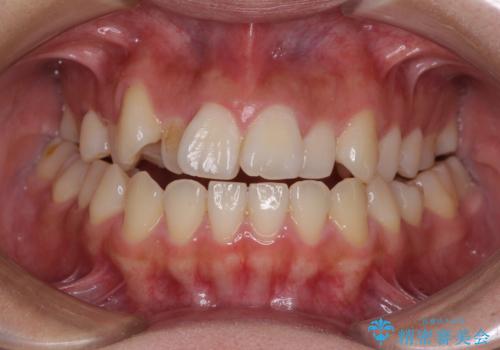

- 前歯の開咬と、上顎前歯の八重歯やデコボコを気にして来院された患者様です。

上顎歯列が狭窄していたため、急速拡大装置により上顎骨を側方に拡大し、その後ワイヤー装置にて矯正治療を行うこととしました。